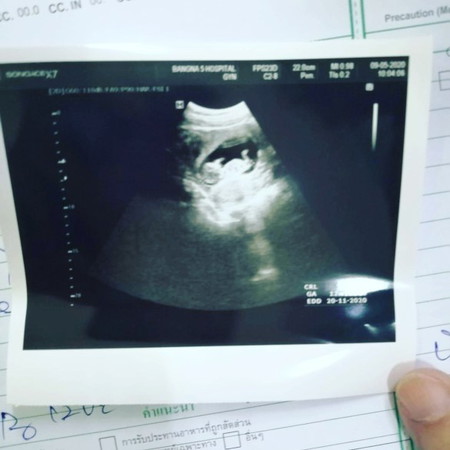

สอบถามหน่อยคับ แฟนผมมีภาวะ แท้ง คุกคาม

เป็นเป็นอันตรายไหมคับ แล้วรักษาได้ไหม เปอร์เซ็นต์แท้ง กับ ไม่แทงอันไหนสูงกว่ากัน แล้วมีใครเคยเป้นไหมคับแล้วปลอดภัยไหม